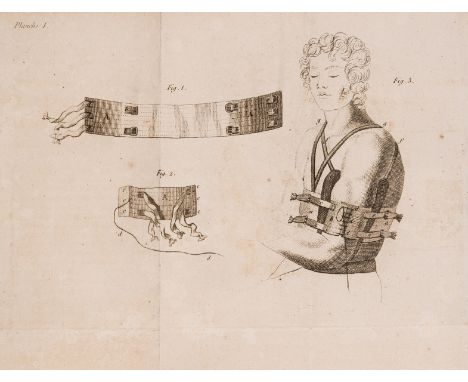

Richter (August Gottlieb) Chirurgische Bibliothek, vol.1-8 only (of 15), first edition, 15 folding engraved plates of surgical instruments and procedures, some foxing, signature cut away from some front free endpapers, most contemporary boards, vol.8 contemporary vellum, Gottingen & Gotha, J.C.Dieterich, 1771-85 § Bohn (Johann) Circulis anatomico-physiologicus seu oeconomia corporis animalis..., second edition, light browning, old library stamp to title, contemporary vellum, morocco label, [Wellcome II.193], Leipzig, T.Fritsch, 1697 § Heister (Lorenz) Chirurgie, in welcher alles, was zur Wund-Artzney gehört..., fourth edition, engraved portrait, title in red & black with old ink signature cut away from foot, 38 folding engraved plates, a few small spots or stains, contemporary half calf, rebacked, [Wellcome II.236], Nuremberg, J.Stein, 1743, all a little rubbed; and 10 others, medicine, German, v.s. (20)⁂ The first is one of the earliest journals devoted to surgery and central to the development of surgery in Germany during the eighteenth century. It includes many contributions from abroad including Percival Pott on palsy, fractures & head wounds, Guerin on eyes, Hunter on teeth, Gesscher on amputation, Juville on hernia, amongst others. The last item is the fourth and much enlarged edition of the one of the most popular surgical texts of the 18th century, which went through many editions. Heister coined the term "tracheotomy" and designed a spinal brace.